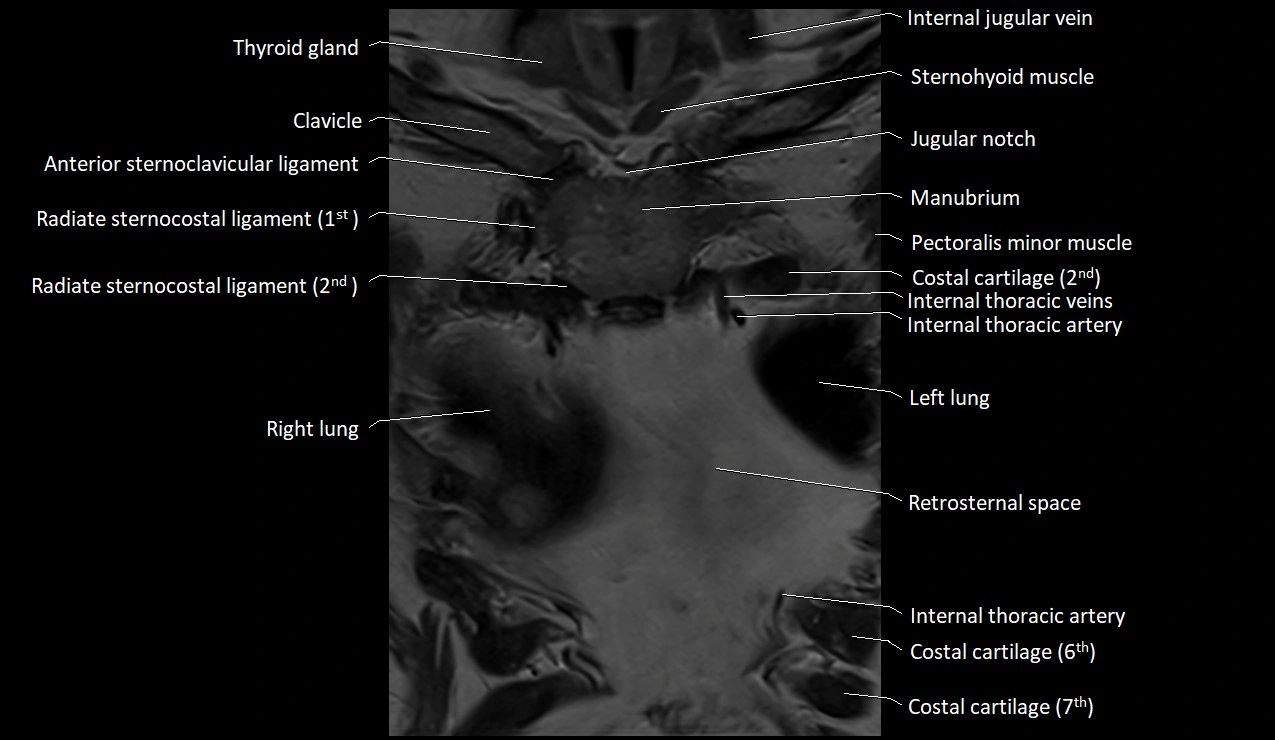

MRI images

image